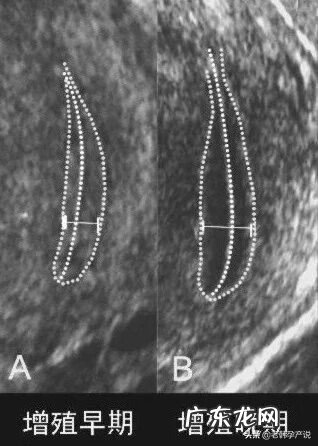

2.增殖期

月经周期的5-14天 。这是内膜从“0”开始逐渐生长的过程,所以这个时期也是内膜最薄的时期,大约在0.5-1.0cm,超声检查可见明显的三线征